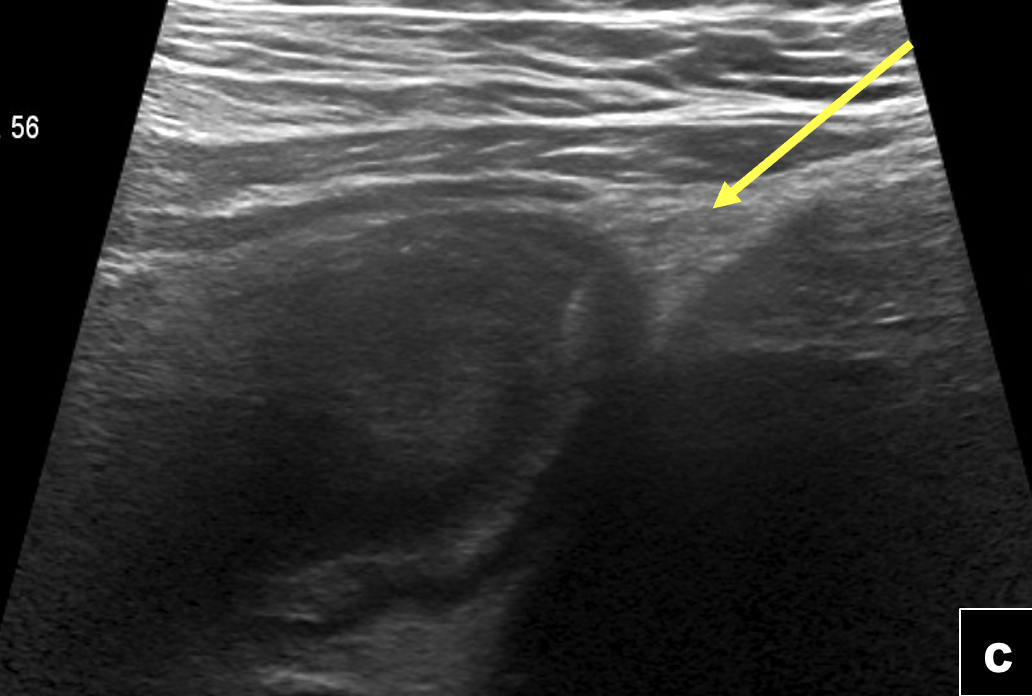

US de abdomen y pelvis: (a) Engrosamiento nodular solido del íleon distal (flecha) vascularizado al Doppler color, (b) el que se continua con imagen quística compleja de gran tamaño ubicada en la fosa iliaca derecha. (c) Engrosamiento parietal difuso de ileón distal visualizado con transductor de alta frecuencia (flecha)